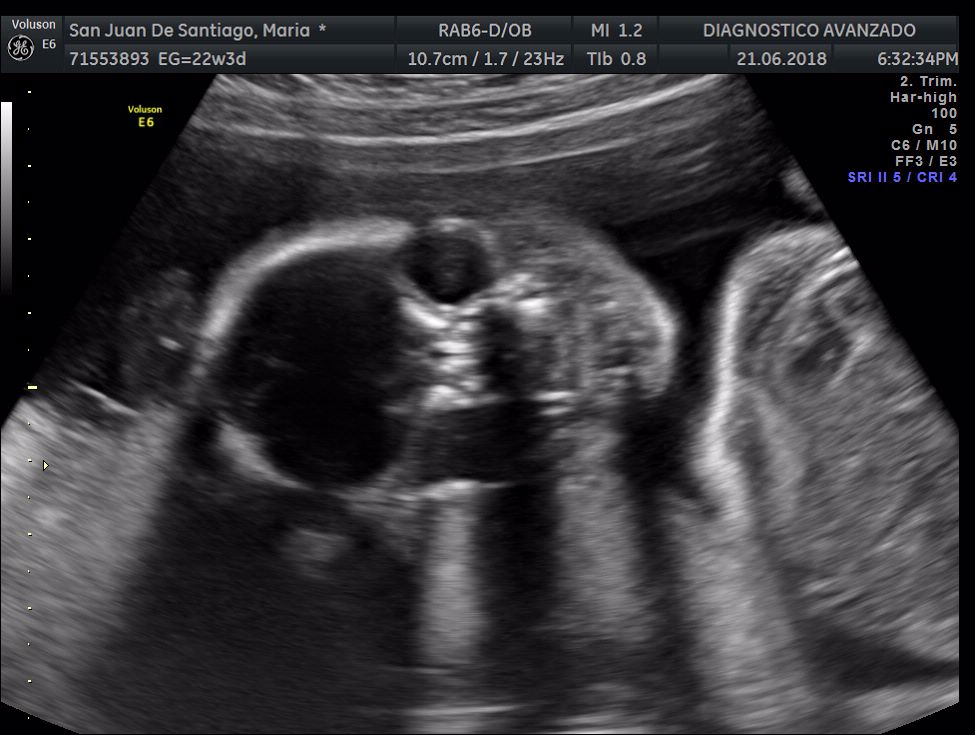

¡Hola a todos! Hoy hemos ido a hacer la tradicional ecografía 3D de la niña, os dejamos todo el material (aunque es un poco demasiado).